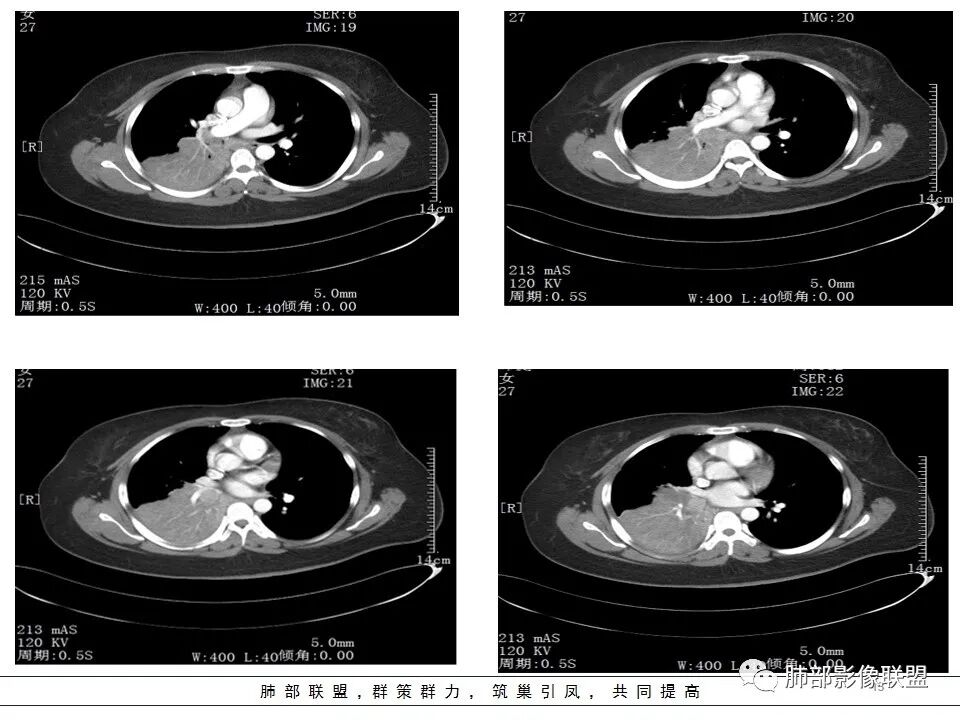

右肺体积缩小,右肺门可见片状影,叶支气管堵塞,呈低密度,无强化,其内似可见点状高密度钙化,病变外周膨隆,右肺下叶大片状致密影,增强后明显强化,其内血管走形自然,右肺下叶呈肺不张改变。纵隔肺门无肿大淋巴结。年轻女性,高热、黄痰来诊。综合考虑:右肺中、下叶综合征合并下叶肺不张,考虑炎性病变,炎性叶支气管阻塞可能性大,早期肺脓肿?结核有点不符合,无胸水,病灶形态太单一。

右肺中叶粘液栓,中叶低密度肿块,密度均匀,延迟强化,右肺下叶不张,考虑炎性病变

右肺下叶肿块,宽基底与胸膜相连,边缘膨隆,近段支气管堵塞,远端胸膜未见栽赃,平扫密度均匀,增强后可见低密度指套征及血管穿行,年轻女性,咳嗽咳痰发热6天,考虑1:淋巴瘤2:SFT3:PNET4:结核

女,27岁,右肺下叶支气管闭塞,圆形软组织肿块和不张肺,增强不均匀强化,见片状坏死,多个纵隔淋巴结肿大,无钙化空洞及卫星灶;考虑恶性占位,肺肉瘤或鳞癌合并肺不张,鉴别诊断:结核,肺脓肿

从CT看难度大。女,27岁,发热6天,咳嗽咳痰3天。无呼吸困难。右中间支气管堵塞?右下肺不张,大支气管堵塞常见原因:结核、肿瘤、异物。无呼吸困难,感觉病程较长,肺不张导致的肺功能下降有一定耐受。堵塞支气管似见低密度病灶,强化不明显,粘液表皮样癌?腺样囊性癌?鳞癌?还是结核?有待支气管镜进一步检查。

首先考虑支气管内肿瘤(如类癌、腺样囊性癌),导致阻塞性不涨

右肺下叶支气管闭塞,圆形软组织肿块和不张肺,增强不均匀强化,见片状坏死,多个纵隔淋巴结肿大,无钙化空洞及卫星灶。鳞癌?肺脓肿?

发热咳嗽,右肺下叶可见团块状实变密度影,局部膨隆,并可见胸膜牵拉,相应下叶支气管未见显示,增强后肿块近端呈不均匀强化,可见大片状坏死,内血管略变细,毛糙,周围肺组织支气管内可见粘液栓形成,另纵膈肿大淋巴结,考虑恶性肿瘤,鳞癌,伴阻塞性肺不张,淋巴结转移

临床发热,腹泻,咳黄痰,应该是感染性病变。影像表现为下叶,中叶支气管堵塞,远端支气管内粘液潴留,所属肺组织不张,膈肌明显升高,上叶代偿性肺气肿,增强似乎可见中间段支气管处一个强化结节,考虑中间段支气管占位性病变合并远端支气管粘液潴留,感染可能,肿瘤性质不好定,太年轻,猜一个,粘液表皮样癌

年轻女性,发热6天,咳嗽咳痰三天

CT扫描示右肺下叶支气管堵塞,类圆形大肿块伴胸膜下大片肺实变影,增强扫描类圆形肿块延迟强化,见少量坏死,余实变区增强可见内部血管走行。纵隔见肿大淋巴结。考虑为恶性病变伴右肺下叶肺不张